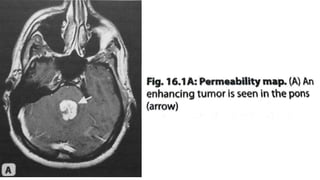

PERMEABILITY OR LEAKINESS

• Increased permeability or leakiness

because of break in BBB results in

accumulation of Gd based contrast in

extravascular space.

• T1 enhancing effects of this extravascular

Gd may predominate to counteract the T2

signal lowering effect of intravascular Gd,

resulting in falsely low rCBV values.

• To reduce permeability induced effects on

rCBV include mathematical calculation of

PERMEABILITY or K2 maps.